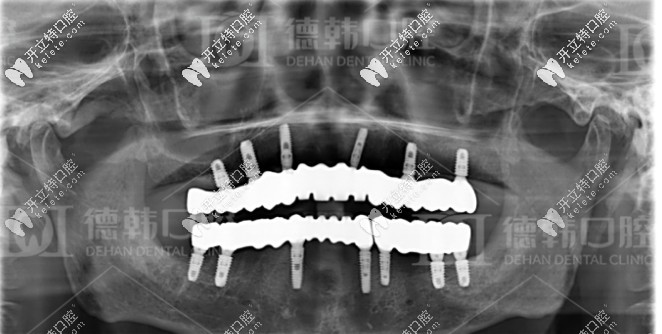

張?jiān)洪L(zhǎng)針對(duì)爺爺年齡大、口腔條件不佳的情況,為其制定了一套即拔即種的全口種植方案:總共種植了13顆種植體,其中下頜種植7顆種植體,十五天后再種植上半口,上頜種植了6顆種植體。

經(jīng)過(guò)種植體埋入、放置基臺(tái)及裝牙冠等流程,一共花費(fèi)了6個(gè)月,爺爺終于恢復(fù)了滿口牙。

種牙成功后的牙片